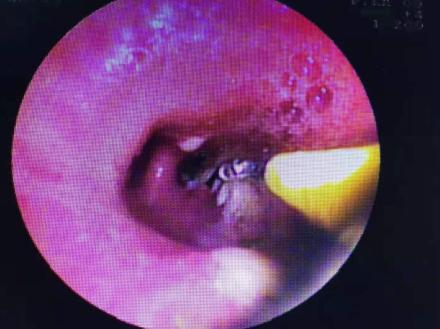

1月25日,科室主任、主任医师黄国民,副主任医师江焰平,护士长曹晖红,主管护师毛景丹等人密切协作,为鲍先生进行了手术,通过电子支气管镜准确找到了异物阻塞的位置,并成功取出了一根长约2cm的锯齿样鱼刺,与之前患者及家属回忆的情形相一致,终于确定了鲍先生长期咳嗽不愈的病因。1月27日,鲍先生的病情恢复良好并出院。